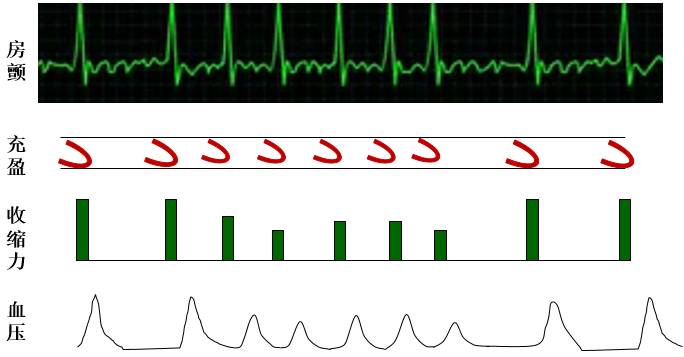

Frank-Starling Law

窦律心室同步

房颤致心室激动不同步